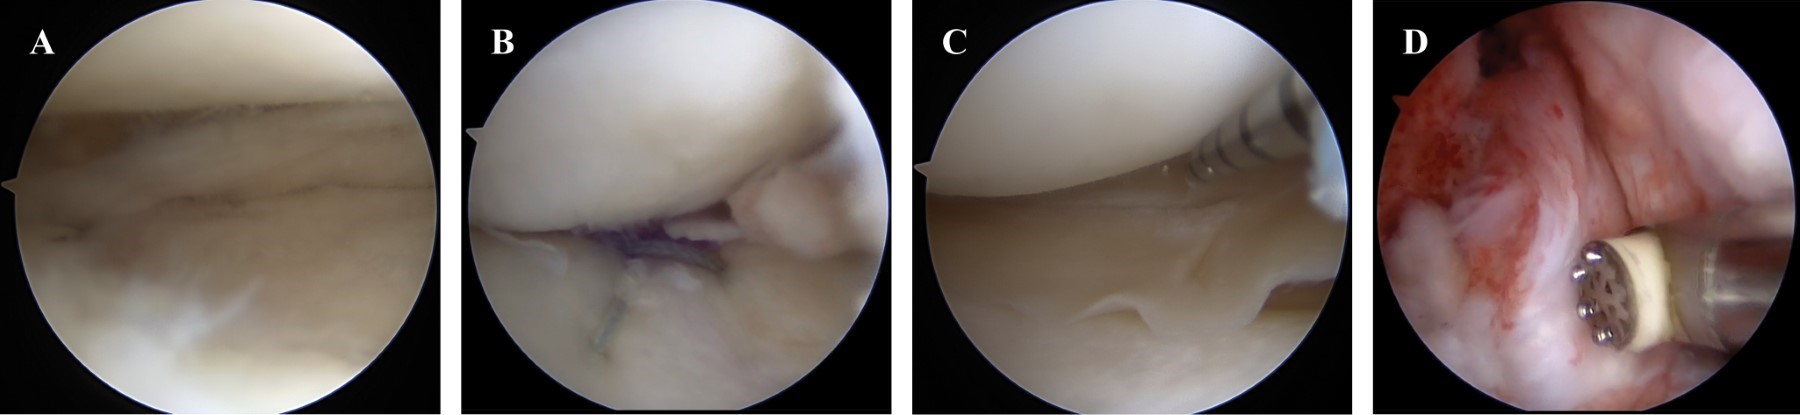

Lateral meniscus transplantation with allograft, a good alternative for the management of postmeniscectomy syndrome in young patients. Presentation of a case

Meniscal injuries represent one of the main causes of intra-articular knee pain, especially in young patients, athletes or those with a high demand for physical activity; representing a challenge for the arthroscopist surgeon due to the great complexity that some of these injuries can present. Currently, the advances that have been implemented in arthroscopy allow us to repair meniscal injuries that in the past were considered irreparable. Although our priority is to preserve as much of the meniscus as possible, there are cases in which the injury reaches such complexity that this is impossible, with partial or total meniscectomy being the only therapeutic option. In the United States, approximately 690,000 partial meniscectomies are performed each year. This situation makes us consider meniscal transplantation as a great therapeutic option for patients considered young enough for joint replacement. The ideal patient is a relatively young patient (between skeletal maturity and 50 years), who has a well-documented history of partial or total meniscectomy, pain well localized to the affected compartment, with failure to conservative treatment and without high-grade chondral defects. in a generalized way. We present the case of a 35-year-old male patient with a history of total meniscectomy of the right lateral meniscus seven years ago, who currently presents with a postmeniscectomy syndrome of the lateral compartment. Due to the clinical and demographic characteristics of our patient, as well as the findings in the imaging studies, meniscal transplantation with allograft represents an excellent alternative to alleviate the symptoms and slow down as much as possible the need for joint replacement as a definitive treatment.

Figure 1

Figure 2

Figure 3

Figure 4

Figure 5

Figure 6

Figure 7

Figure 8